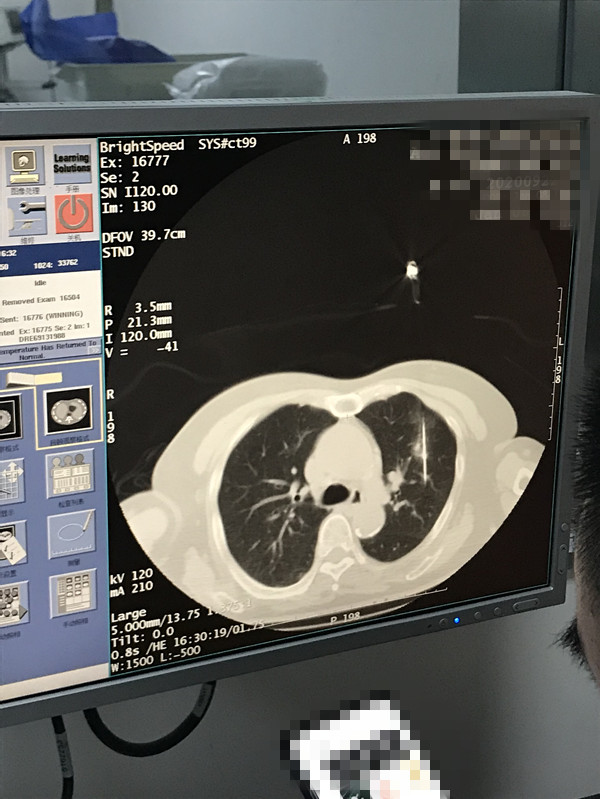

下一篇:2021年1月份肺部氩氦刀手术